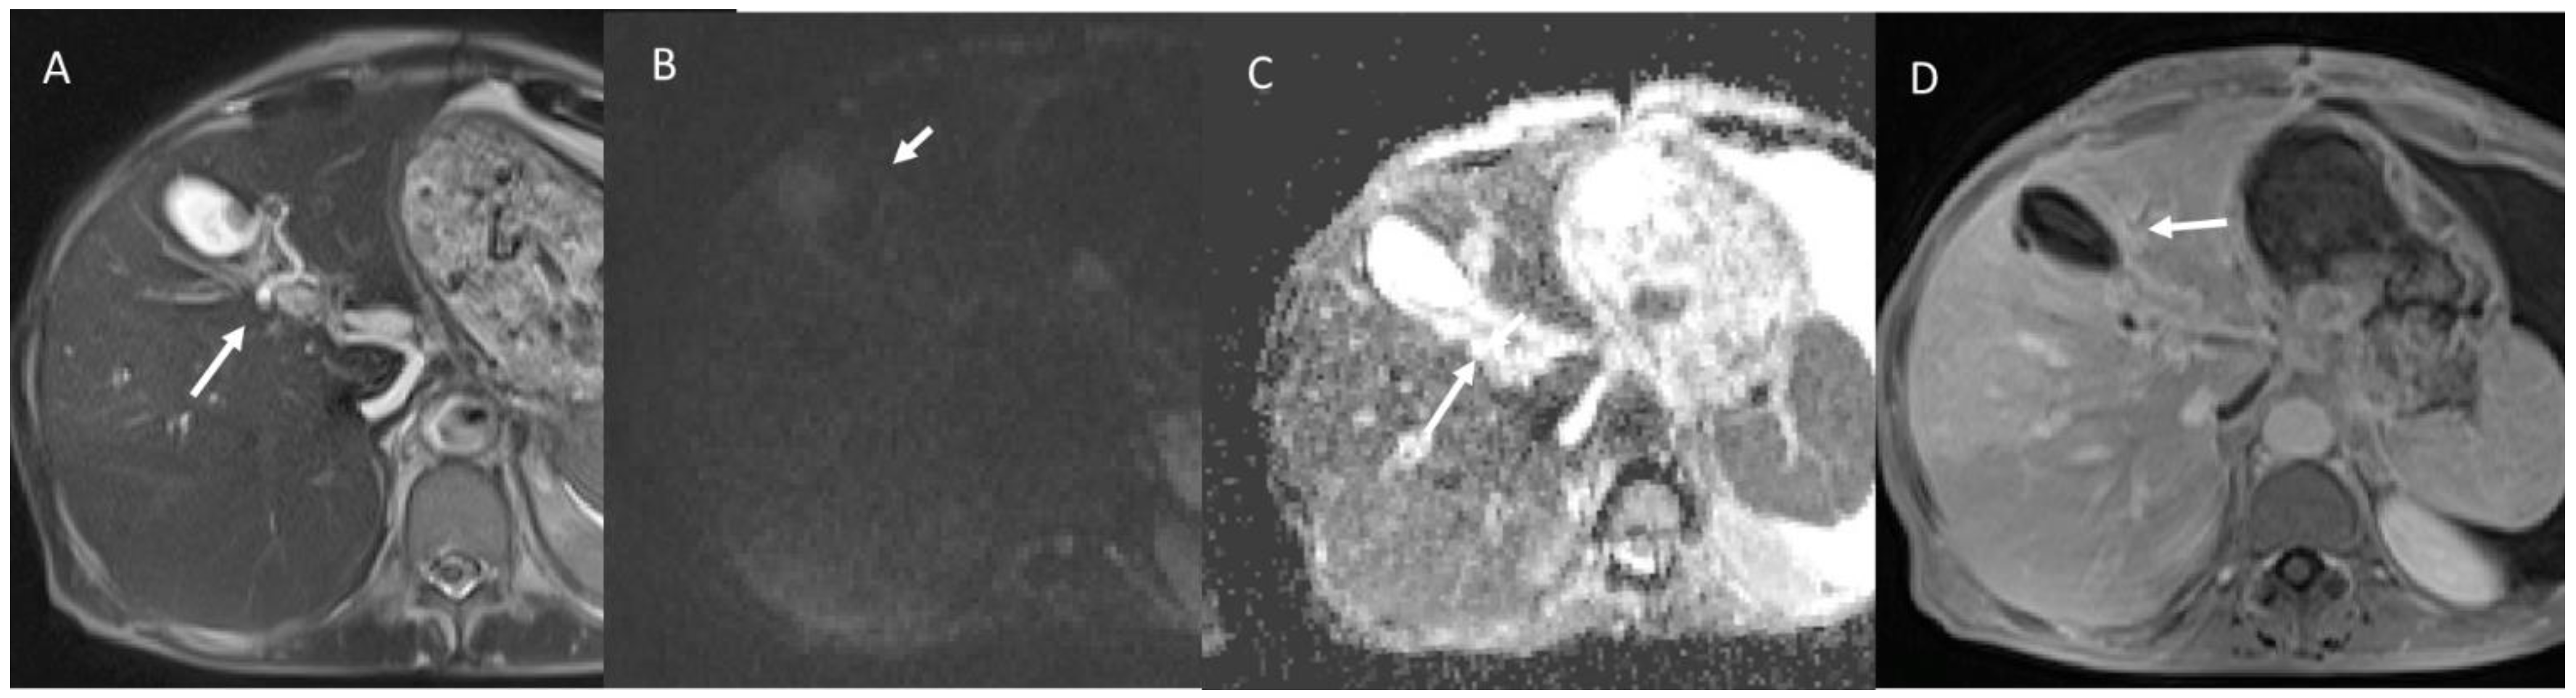

3. Primary Sclerosing Cholangitis

6.5. Diagnostic Management